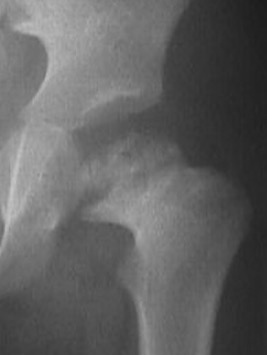

AP X-ray

Timing

AP after 6 months of age when the superior femoral epiphysis becomes ossified

Create 4 quadrants on xray

- Hilgenreiner's Line - horizontal through triradiate cartilages

- Perkin's Line - vertical through lateral edge of bony acetabulum

- superior femoral epiphysis (SFE) should be in inner and lower quadrant

Dislocated hip with smaller superior femoral epiphysis (SFE) and location in the upper outer quadrant

Findings

| Superior femoral epiphysis | Disrupted Shenton's line | Increased acetabular index | Increased head to teardrop distance |

|---|---|---|---|

|

Smaller

In upper/ outer quadrant |

Line along inferior neck

Line inferior border superior ramus |

Angle between Hilgenreiner's line and acetabular line |

Lateral tear drop to medial ossification center |

Normal < 30° DDH > 35° |